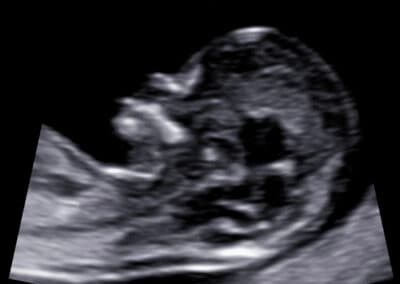

Vyšetření nosní kůstky – nosní kůstka je přítomna

Vyšetření nosní kůstky – nosní kůstka není přítomna

UZ vyšetření nosní kůstky dle FMF protokolu

Protokol pro správné vyšetření nosní kůstky:

CRL 45-84 mm (11-13+6 týden) Přesná mid-sagitální rovina (echogenní špička nosu a patro vpředu, diencefalon v centru mozku a nuchální translucence vzadu, nesmí být vidět processus frontalis maxillae) Zvětšení (hlava a hrudník plodu vyplňují většinu obrazovky) Paralelní průběh povrchu sondy s povrchem nosu Separace nosní kůstky od kůže (dvě echogenní linky) Echogenita nosní kůstky musí být při její přítomnosti vyšší než je echogenita kůže na povrchu nosu Pokud je linka nosní kůstky tenčí a méně echogenní než je linka povrchu kůže nosu, jedná se abnormální nález- nosní kůstka chybí